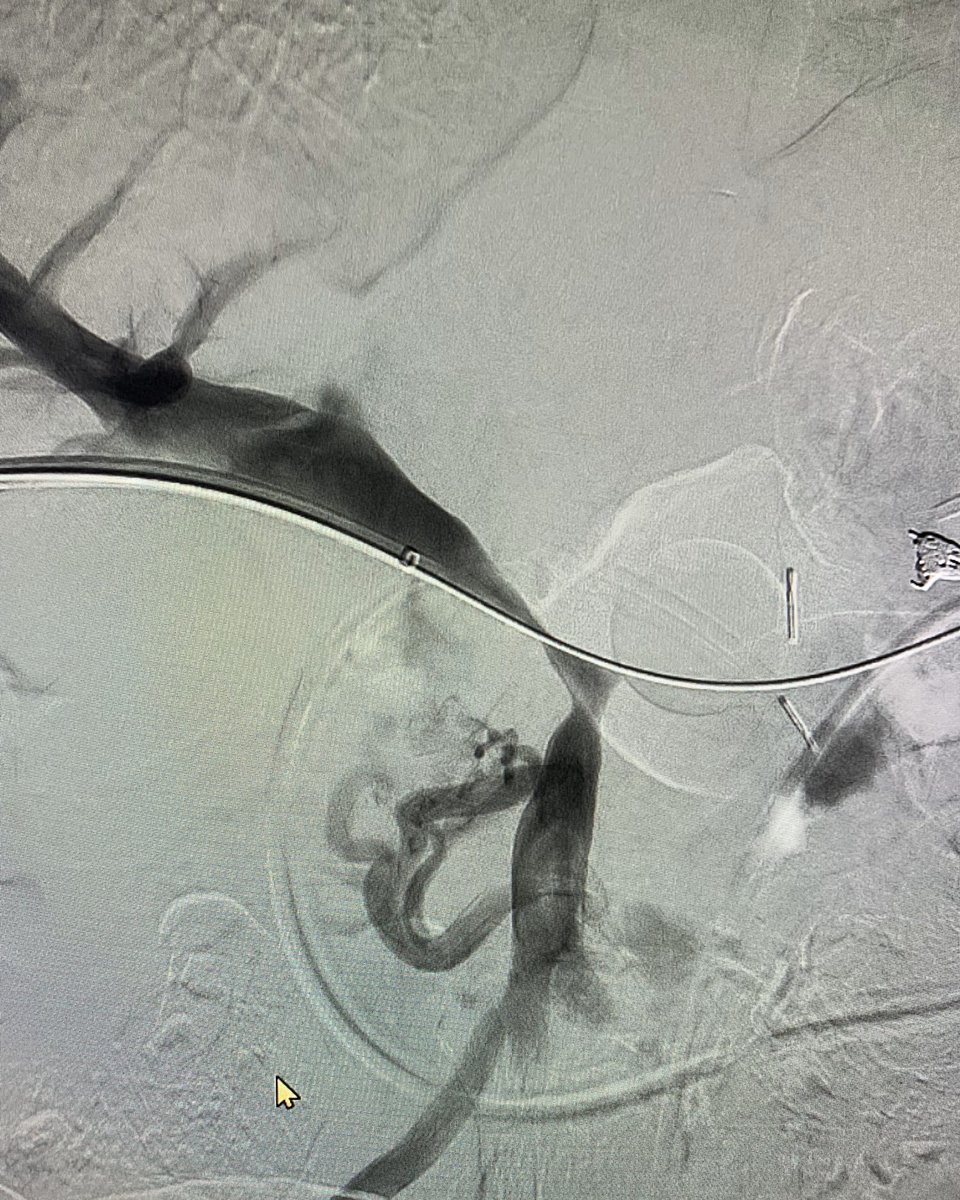

When

#filterout is not an option,#stent exclusion helps. 2 IRs, 3 RT’s and 4 hrs later,#trapease (8yr)#occlusion#device successfully excluded. Thanks Buckley from@BDandCo for#venovo support.#irad#TwittIR@SIRspecialists@SIR_ECS@SIRRFS@CVIR_Journal@JVIRmedia@EVTodaypic.twitter.com/qxKOWEu3bJ